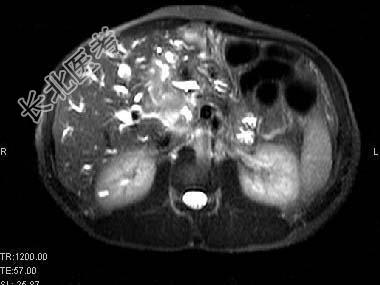

- 单项选择题根据所提供的图像,最可能的诊断是 ( )

A、肝囊肿

B、肝脓肿

C、先天性胆管扩张

D、胆管细胞癌肝内转移

E、以上都不是